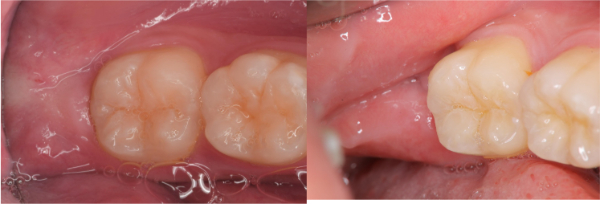

術前、術後比較